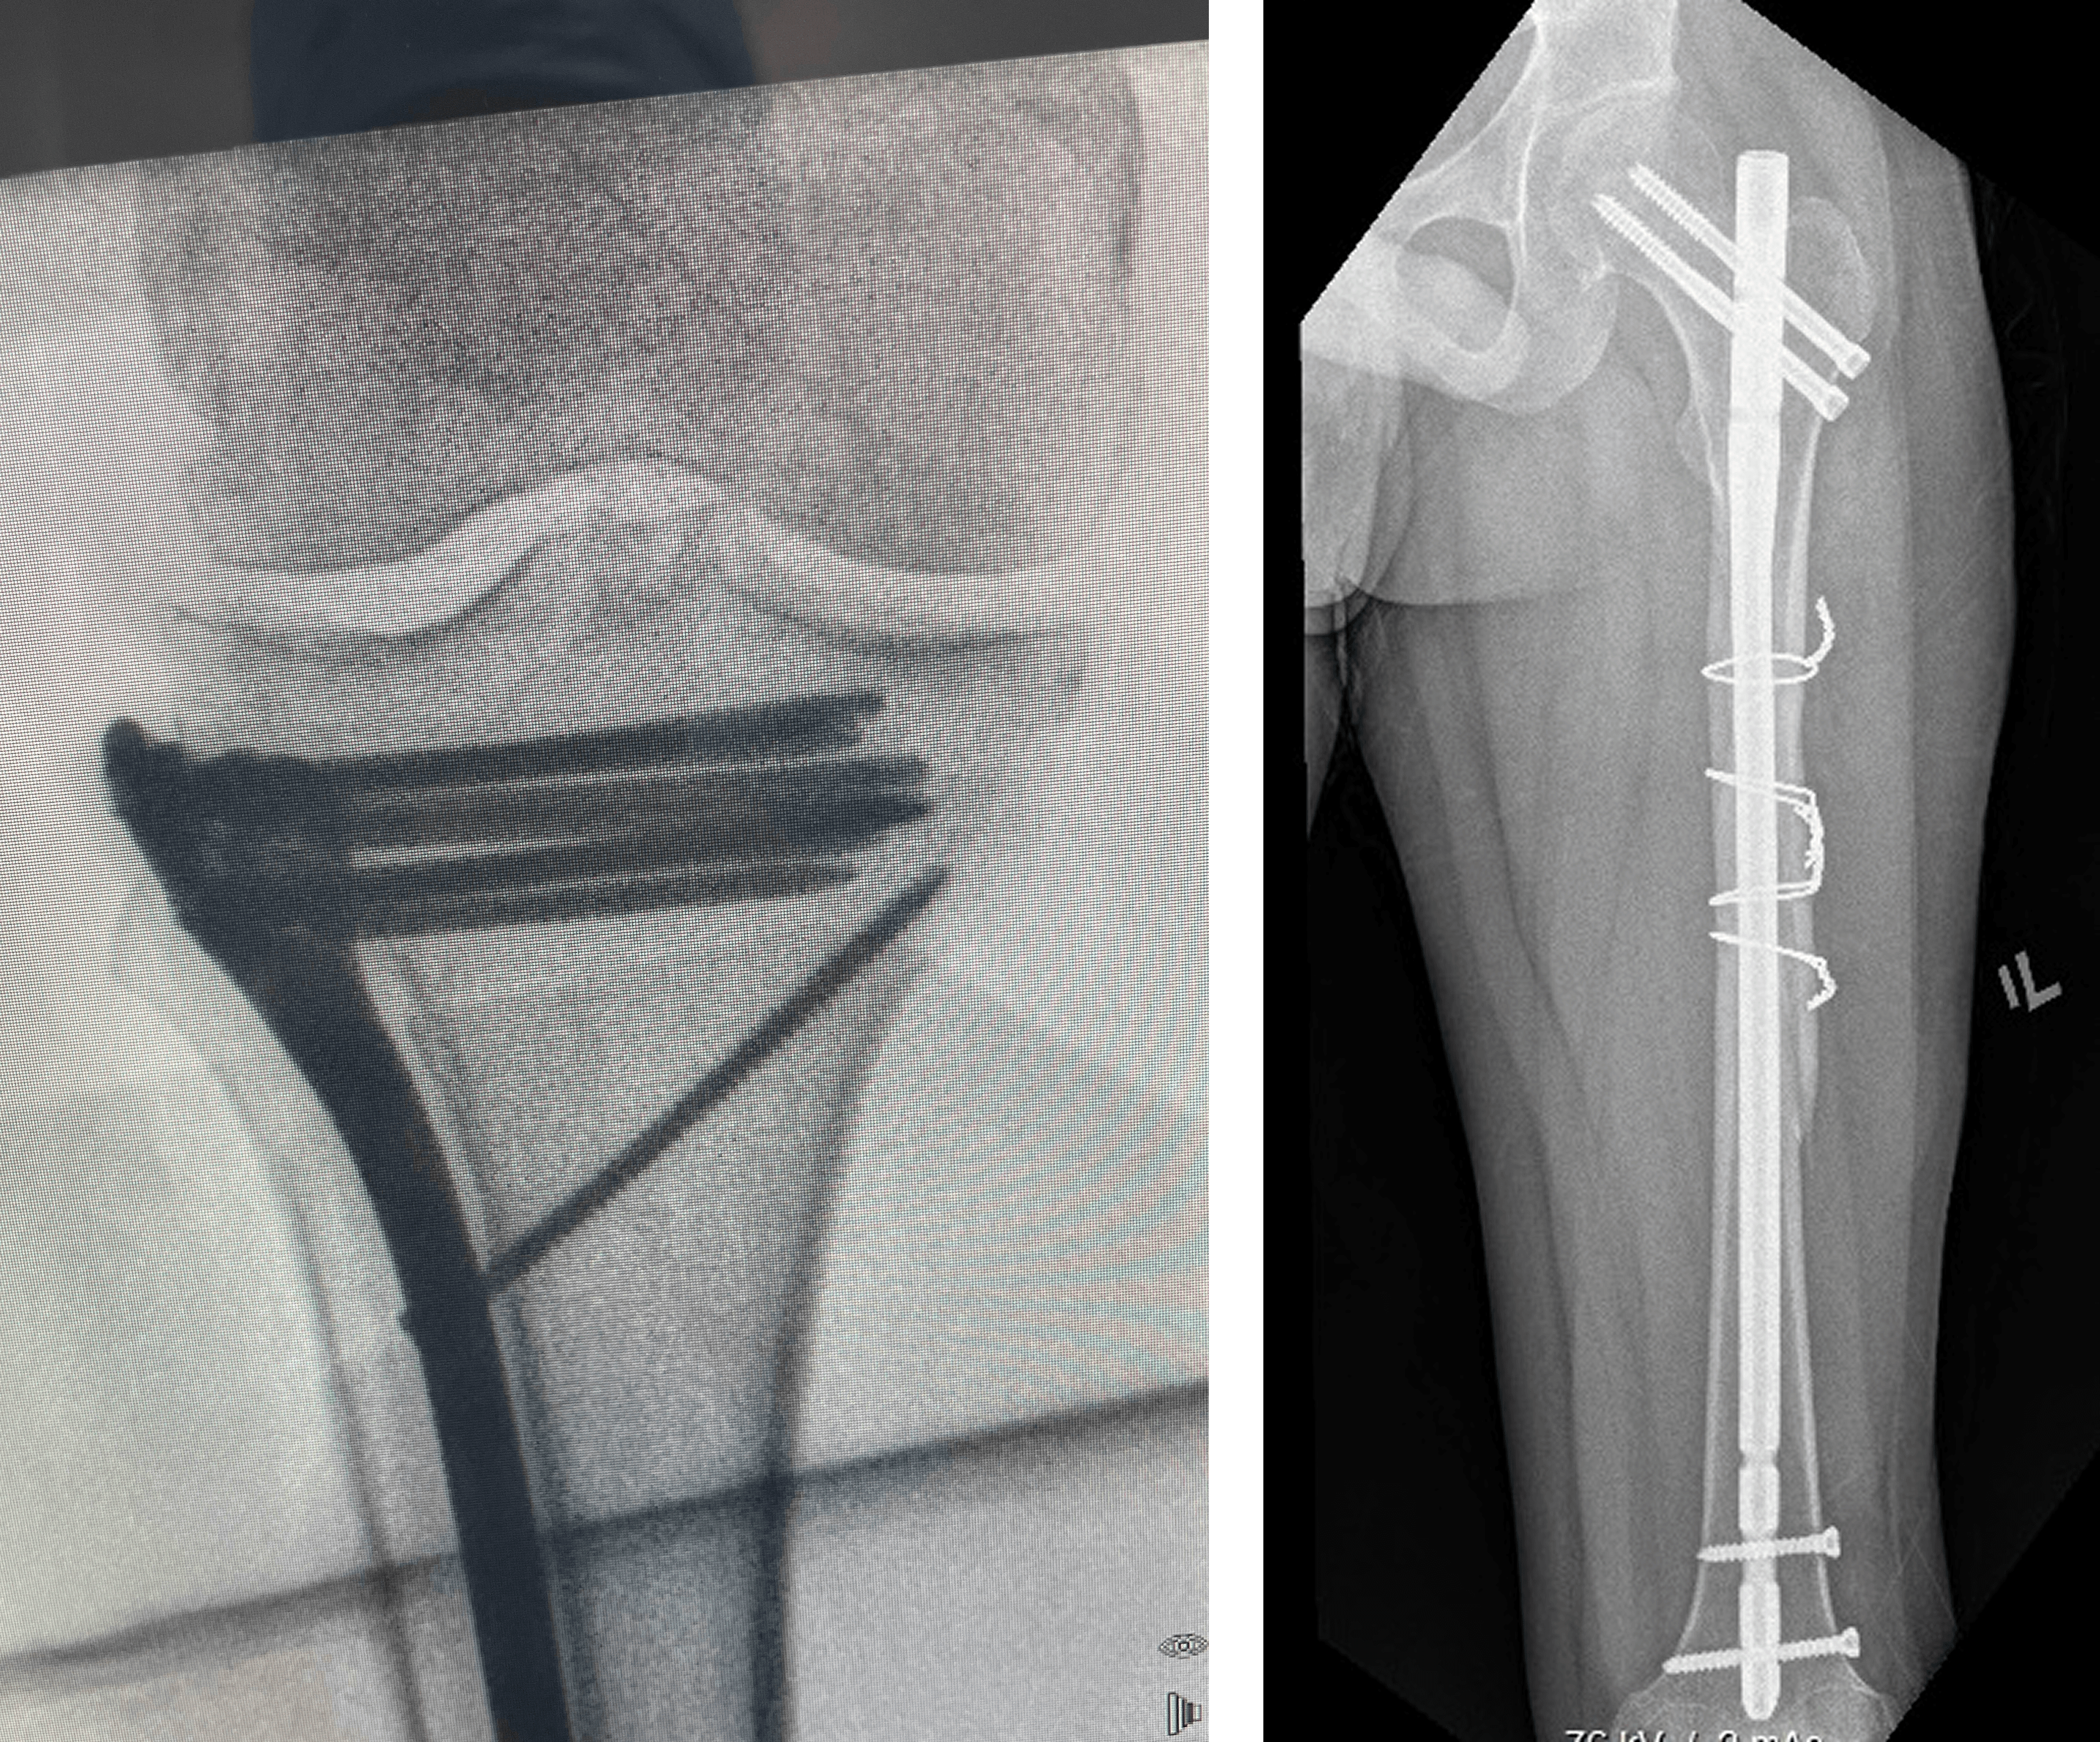

X-rays: To detect fractures or dislocations

Repair of fractures, dislocations, tendons, or ligaments